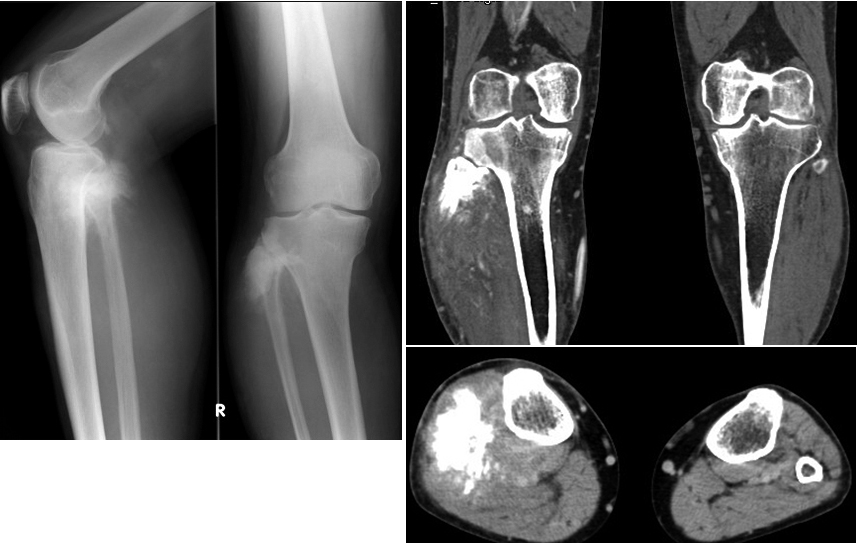

骨の周囲の痛みや腫れのために医療機関を受診した場合、医師は画像検査を指示する可能性があります。これらには次のものが含まれる場合があります。

- X線

- MRI

- CTスキャン

これらの検査は、腫れや痛みの根本的な原因を特定するのに役立ちます。タマネギの皮の骨膜反応は、複数の層の骨のように見えます。

タマネギの皮膚の骨膜反応は、ユーイング肉腫などの疾患の存在を示している可能性があります。良性腫瘍の結果である可能性もあります。